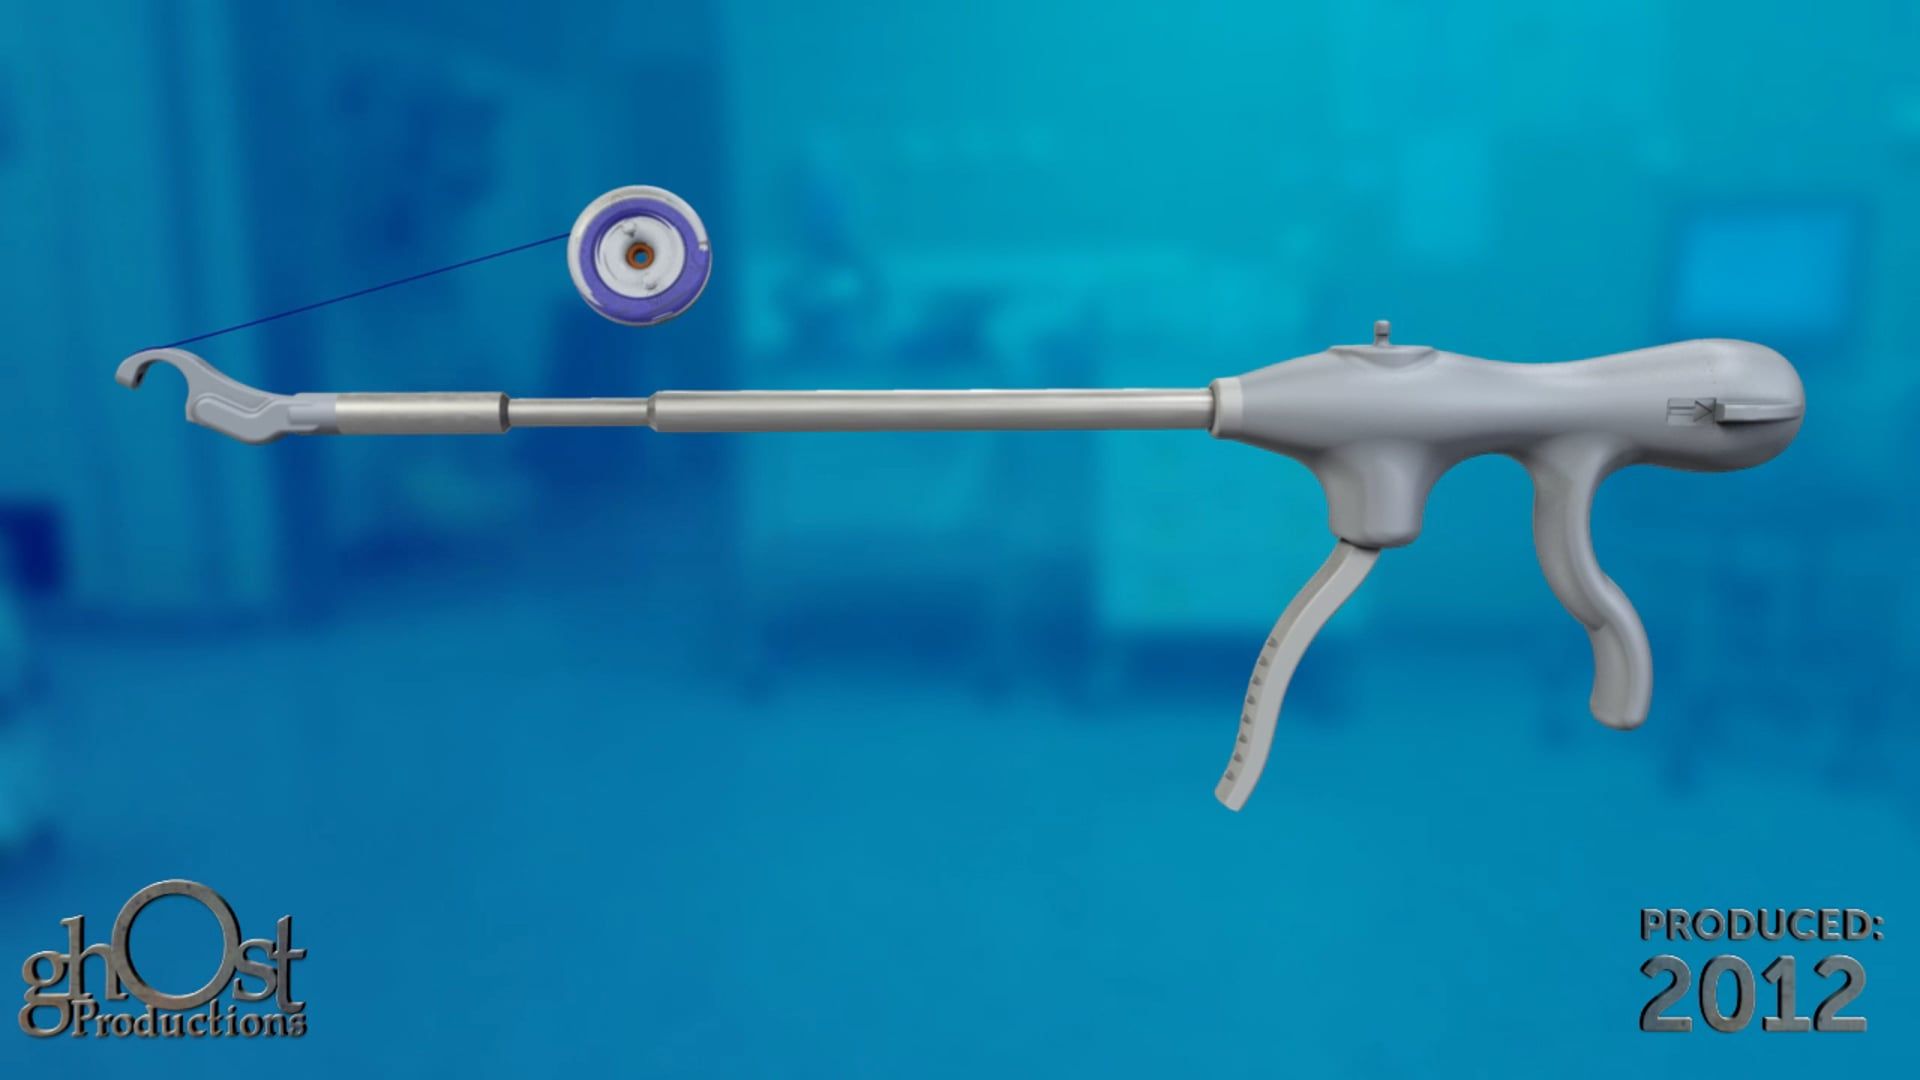

Discover the AMS Continuum, a reliable and innovative bladder anchored urinary catheter with retractable tines, through this stunning animation.

Looking for a reliable and effective bladder anchored urinary catheter with retractable tines? Look no further than the AMS Continuum, brought to life in stunning detail in this animation from Ghost Productions. Our team worked closely with American Medical Systems to create a visual representation of this innovative medical device, highlighting its unique features and benefits. Whether you're a healthcare provider looking for the latest in urinary catheter technology or a patient seeking a more comfortable and secure solution, the AMS Continuum is a game-changer. Watch our animation today to learn more!